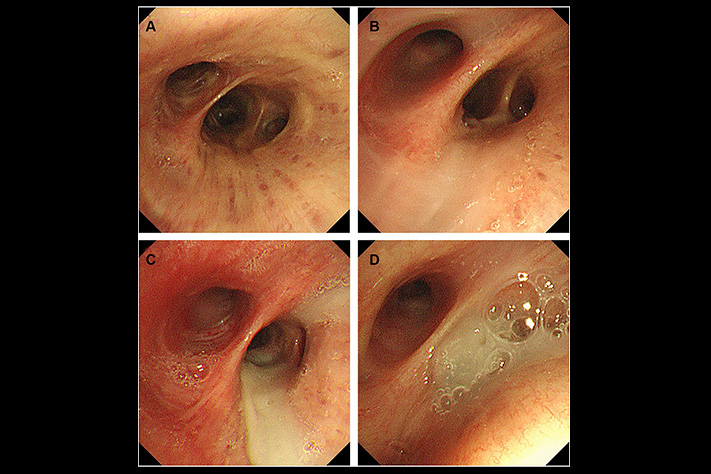

What they found: In every single patient's airways, there was a dense layer of mucus at the very bottom-below the fresh mucus, below where any treatment could reach.

The cilia-those tiny hairs that sweep mucus out-were completely buried under it. Non-functional.

He showed her a diagram. "This is what you cough up every morning. Fresh mucus. Mucinex thins this. Your nebulizer helps with this."

Then he pointed lower. "But underneath, there's another layer. Old mucus. Months old, maybe years. Your cilia are buried under it."

"When you lie down, gravity shifts it up. Blocks your airway. That's why you wake up choking. That's why nothing you've tried has worked."

He pointed to the bottom layer again. "That's the difference. Everything you've tried works on what you can cough up. But this layer? It's too deep. Too hardened. Surface treatments can't touch it."